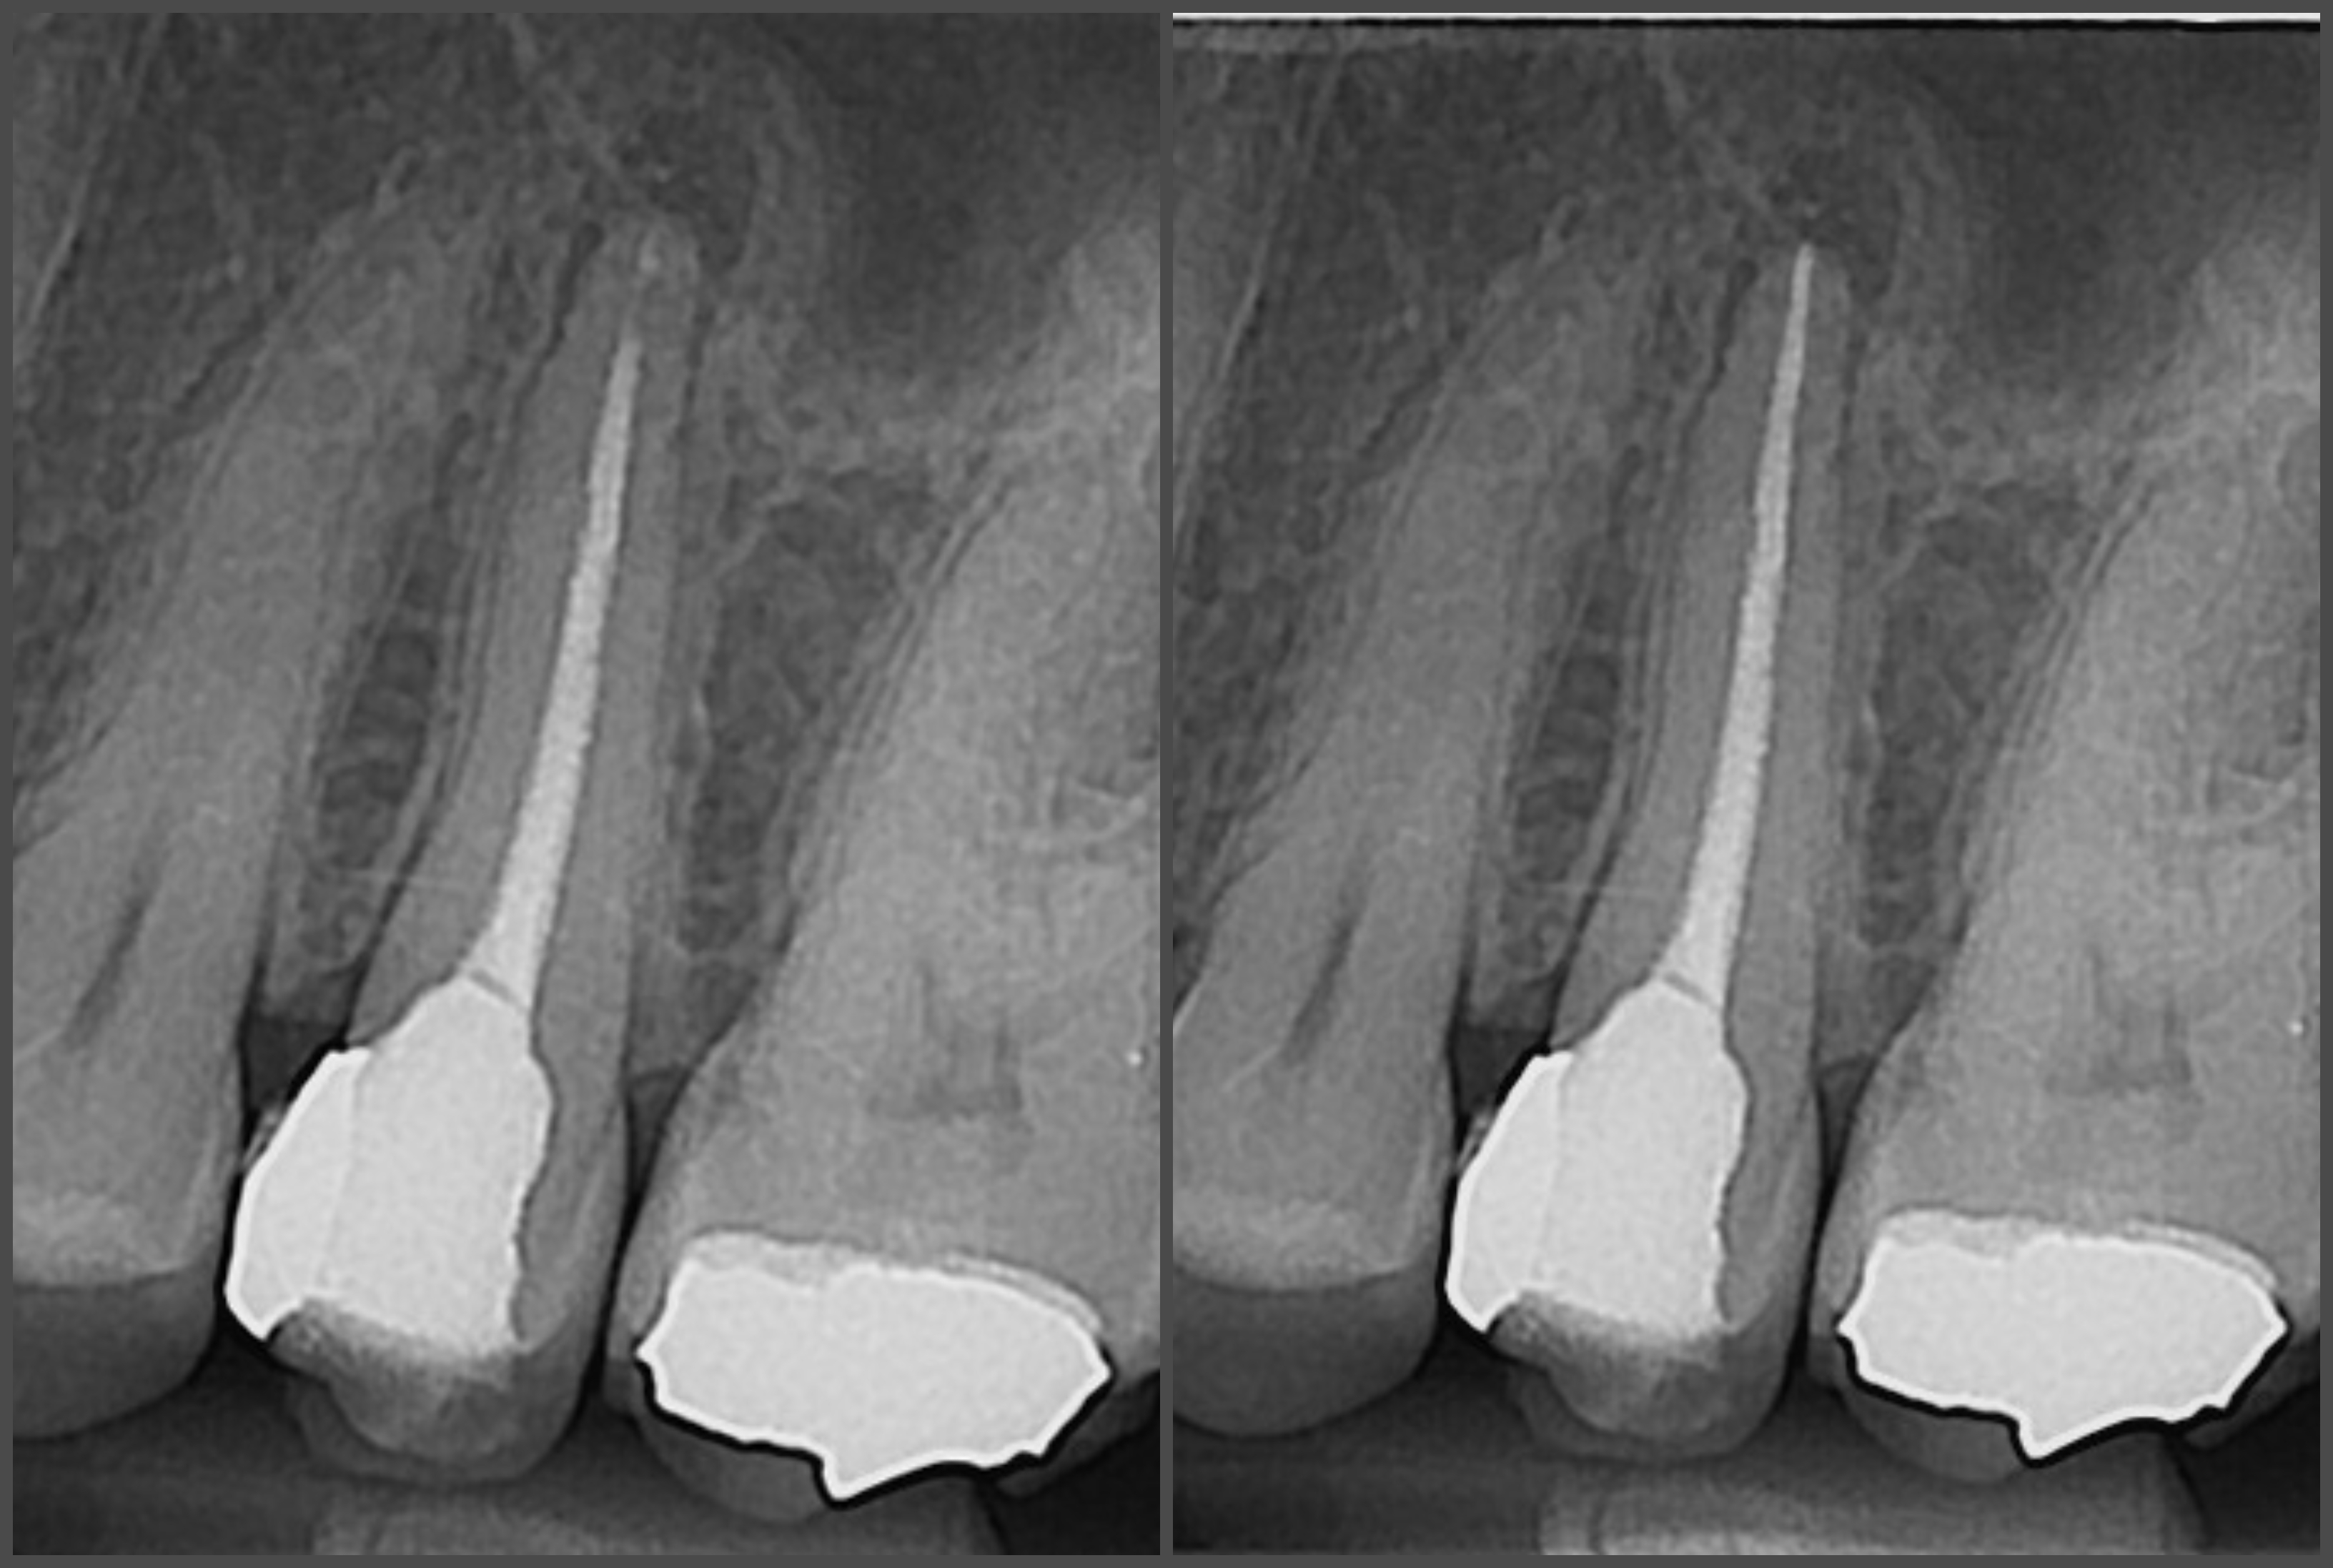

Endodontska terapija provodi se kada karijes uništi zub (caklinu i dentin) te dođe do živca (pulpe).

Ako se zub s upalnim procesom ne liječi, dolazi do širenja upale na kost i stvaranja upalnog procesa oko vrha korijena, odnosno dolazi do razvoja granuloma.

Endodontska terapija započinje uklanjanjem karijesom zahvaćenog zubnog tkiva, nakon čega se odstranjuje upaljena zubna pulpa te se kemijski i mehanički čisti zubni kanal radi uklanjanja bakterija i inficiranog dentina.